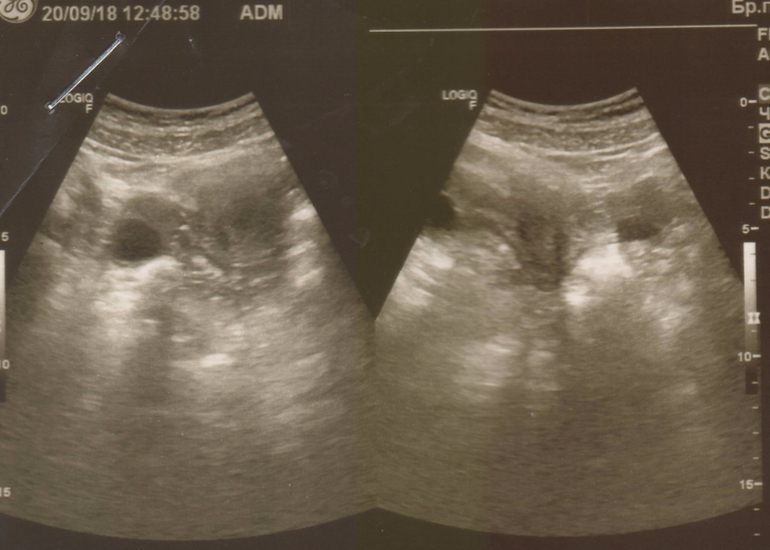

Желтое тело на УЗИ

Желтое тело можно обнаружить во время диагностической процедуры, если УЗИ пришлось на период сразу после овуляции. Это подтверждает, что цикл овуляторный и сама овуляция прошла нормально.

Желтое тело можно увидеть на трансабдоминальном и трансвагинальном УЗИ органов малого таза. Для женщин, живущих половой жизнью, более точным вариантом будет трансвагинальное исследование.

На экране аппарата врач УЗИ увидит неоднородное округлое образование. Появляется желтое тело в правом или левом яичнике в зависимости от локализации созревания доминантного фолликула и овуляторной яйцеклетки. Сторона созревания не имеет принципиального значения для будущей беременности и здоровья женщины.